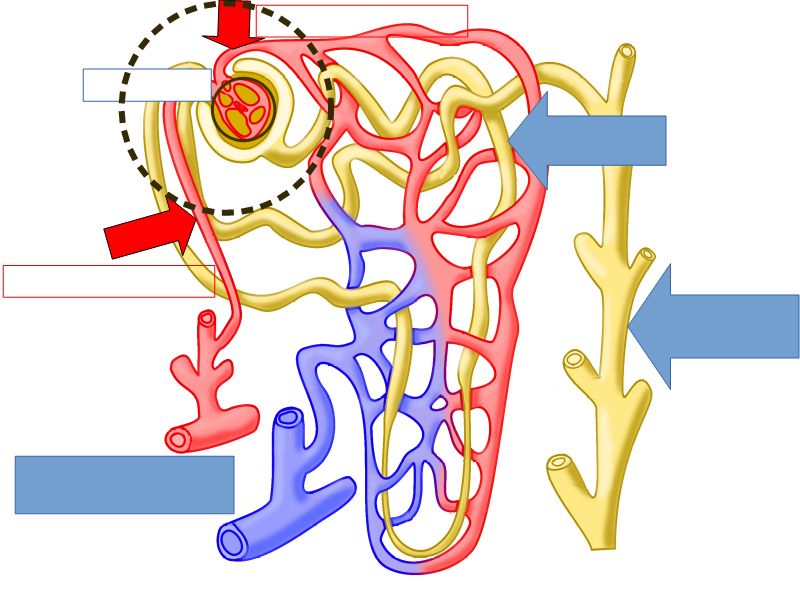

Nephron

- Unit responsible for

- Filtration

- Excretion

- Resorption

- Include

- Kidney tubule

- Glomerulus

- Exclude

- Collecting tubule

Nephron

- Renal corpuscle

- Proximal convoluted segment

- Long loop of Henle

- Descending portion

- Ascending portion

- Distal convoluted segment

Blood flow

- Efferent arteriole

- Smooth muscle in media

- Capillaries

- Fenestrated

- Afferent arteriole

- Smooth muscle in media